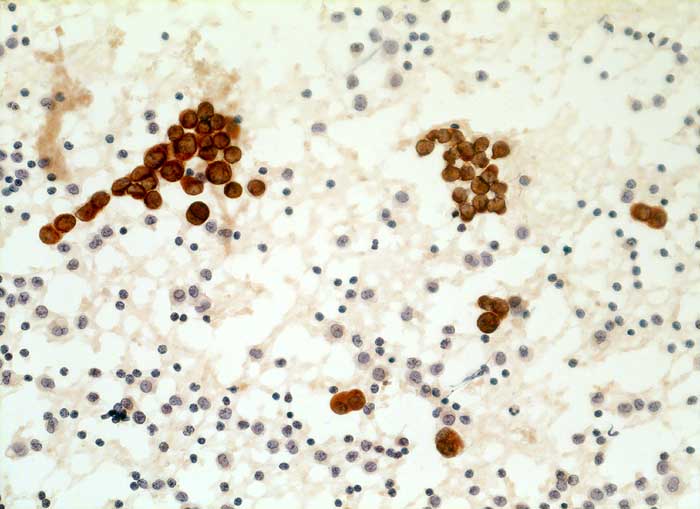

l/ Panzytokeratin (CK22/Lu-5)

Panzytokeratin (CK22/Lu-5)

Anfärbung:

Zytoplasma positiv.

Reaktion in Neoplasien:

Die meisten Karzinome und vereinzelte Sarkome reagieren positiv mit diesen Panzytokeratinen. CK22 ist etwas sensitiver und spezifischer als Lu-5. Entdifferenzierte oder sarkomatoide Karzinome können die Positivität für Zytokeratine verlieren.

Diagnostischer Nutzen:

Suchantikörper zur Abgrenzung von Karzinomen von Lymphomen, Sarkomen und malignen Melanomen. Identifikation von Karzinommikrometastasen in Lymphknoten.